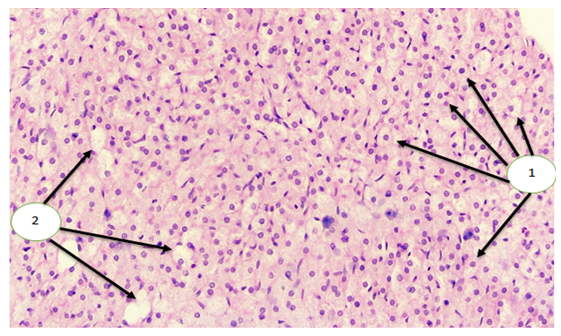

The research was conducted at the Bukhara State Medical Institute named after Abu Ali ibn Sina. For this experimental scientific study, white outbred sexually mature rats of both sexes were selected as subjects, weighing between 130 and 150 grams and aged 90 days. Traumatic brain injury (TBI) was experimentally modeled using a device designed to simulate a road traffic accident, thereby inducing TBI in the laboratory rats. On the 7th day after the experiment, the animals were dissected, and their adrenal glands were extracted for further examination of the morphostructural changes in the layers of the adrenal cortex. The morphological appearance of the adrenal glands in white outbred rats on the 7th day after experimental TBI was as follows: Upon macroscopic examination, the adrenal glands were found to be reduced [4] in size compared to earlier time points. The usual rounded shape was absent, particularly in comparison with day 3 after TBI. In the subcapsular region of the cortex, thickened layers were identified in the intercellular spaces, and a slight, localized edema of the stromal tissue was observed. The adrenal capillaries were dilated and hyperemic, mainly located in the fascicular zone. [3] The number of hyperemic capillaries per 0.01 mm², evenly distributed in both the fascicular and reticular zones, was 2.7. Tissue edema and hypertrophy of adrenocorticocytes contributed to a slight thickening of both the fascicular and reticular zones. [6] In the inner part of the fascicular zone, the typical columnar structure was disrupted. Lipid accumulation in cortical cells was observed in all experimental animals. [5] | Figure 1. Macroscopic specimen. Adrenal gland on the 7th day after experimental modeling of traumatic brain injury (TBI) |

| Figure 2. Microscopic specimen. Adrenal cortex on the 7th day after TBI. Hypertrophy of adrenocorticocytes (1), stromal edema, and thickening of the fascicular and reticular zones (2) are observed. Stained with H&E. Magnification: objective 40×, ocular 20× |